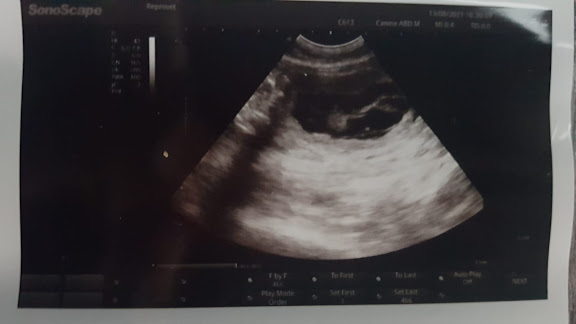

Sitten odotettiin 4 viikkoa, jotta päästiin ultraan, joka paljasti neidin olevan paksuna. Ainakin 5 pentua löytyi, mutta siinähän on mahdollisuus että joku pentu on jäänyt piiloon. Ja onhan tässä mahdollista että osa vielä menetetään. Mutta Lara jäi ultran jälkeen virallisesti mammalomalle.

| Päiviä 30, ei vielä mitään isoa pömppistä. |